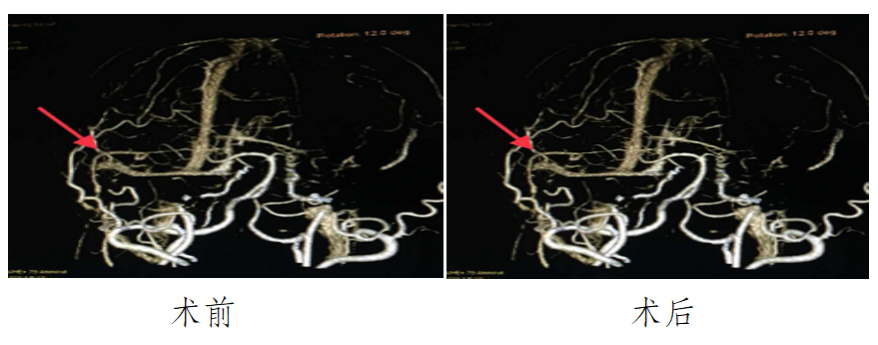

血管搭桥技术治疗烟雾病